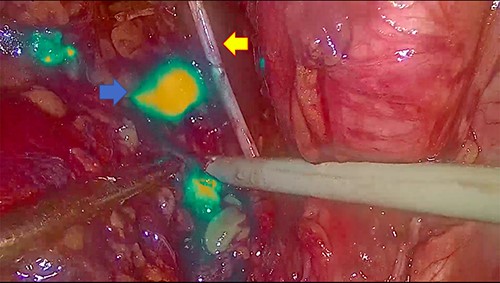

In November 2020, for a diagnosis of prostate cancer at prostatic biopsy, we intraoperatively performed ICG fluorescence-guided lymphography during a laparoscopic radical prostatectomy with pelvic lymphadenectomy. ICG was injected in the prostatic tissue of the patient transrectally through ultrasound identification of the gland. A fine needle was used connected to a 10 cc syringe, taking care to aspirate before injecting the tracer in order to avoid blood vessels. A dedicated laparoscopic high-definition camera system, provided by Karl Storz, was used in our case. This system allowed the surgeon to easily switch from White Light (WL) mode to ICG mode. For this reason, it was very simple to compare WL and ICG mode images. Furthermore, this technique is inexpensive, requiring only a small dose of ICG. Therefore, soon after ICG injection, the lymphatic vessels were identified in the pelvic cavity as fluorescent linear structures running side by side to the iliac vessels. Figure 1 shows the fluorescent lymph nodes in the obturator fossa. Then, using the ‘intensity map’ function (also called ‘overlay function’), lymph nodes can be seen as white structures as this function uses WL (instead of blue light) and eliminates the colors, as shown in Fig. 2. Surgical dissection was therefore performed, avoiding iatrogenic damage to major lymphatic structures. On histological examination, the prostate gland was found to be affected by an acinar adenocarcinoma (with Gleason Score 8, 4 + 4) involving ~20% of the right lobe and 35% of the left lobe. Twenty-four lymph nodes sent as obturators (15 on the right and 9 on the left side) and 10 lymph nodes sent as external iliacs (6 on the right and 4 on the left side) were free from metastases. The patient was discharged 5 days after surgery, and 6 months after surgery, he did not show any complications related to lymph node dissection.

The blue arrow shows the lymph nodes which, due to the effect of indocyanine, take on a fluorescent green color. The yellow arrow indicates the obturator nerve.